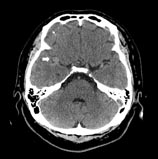

現行的做法是,如果病人描述的頭痛符合雷擊式頭痛的特徵,醫師就會安排檢查去排除是不是有動脈瘤。值得注意的是,有些病患在動脈瘤真的要破裂前的幾天到幾週,有比較輕微的頭痛,就像預告即將到來的災難,被稱為警告頭痛(warning Headache)或是哨兵式頭痛(Sentinel Headache)。筆者在多年前遇到一個病人,因為近來幾天屢屢發作輕微頭痛,醫師安排了電腦斷層並轉來我的門診。預定返診當天早上,病人覺得已經不再頭痛不想來,但太太覺得不妥而代替他來看報告。我在斷層中發現一個動脈瘤(如:圖A),大驚之餘要求馬上帶病人來急診,不料等太太回到家,動脈瘤竟已破裂出血(如:圖B),病人癱瘓在地。經送來急診及後續開刀,雖有改善,仍殘留肢體無力等症狀。後經病人同意,我把這個案例發表在《台灣神經學雜誌》上。

圖A:箭頭所指處即為動脈瘤,直徑約為7毫米。